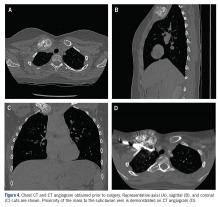

The patient was evaluated by a pediatric hematologist/oncologist 2 weeks later after having obtained the biopsy and a PET/CT scan. At that time, the PET/CT showed an FDG-avid mass at the clavicle without evidence of pulmonary metastatic disease (Figure 3) . She was subsequently evaluated by orthopedic oncology, at which time a discussion was had regarding further treatment. There was essentially no literature to guide the surgical and medical teams, as low-grade clavicular OS is unknown. Based on the evidence of localized, low-grade disease, the determination was made to proceedwith surgical resection. In the event that high-grade disease was identified at the time of final pathological evaluation, the pediatric hematology/oncology team felt that administering all of the patient’s chemotherapy postoperatively would be acceptable and not affect her long-term prognosis. CT and CT angiogram were obtained for further operative planning (Figure 4) .